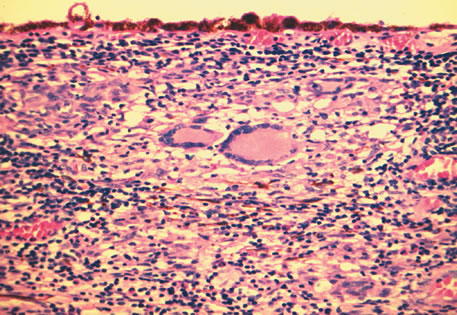

Three histologic patterns of granulomatous inflammation may be seen: diffuse, discrete, and zonal. In diffuse granulomatous inflammation, the epithelioid histiocytes are scattered throughout the involved uveal tissue (Fig. 19). There may be an accompanying background of lymphocytes and plasma cells. Discrete granulomatous inflammation reveals well-circumscribed areas of epithelioid histiocytes (Fig. 20). Zonal granulomatous inflammation consists of a central zone of necrosis and/or polymorphonuclear leukocytes surrounded by epithelioid histiocytes, which is in turn surrounded by a zone of non-granulomatous inflammation consisting of granulation tissue, lymphocytes and plasma cells (Fig. 21).

Fig. 21. Tuberculous choroiditis. A zonal granulomatous inflammation is present. Central area shows necrosis. (Hemotoxylin-eosin ×65.)